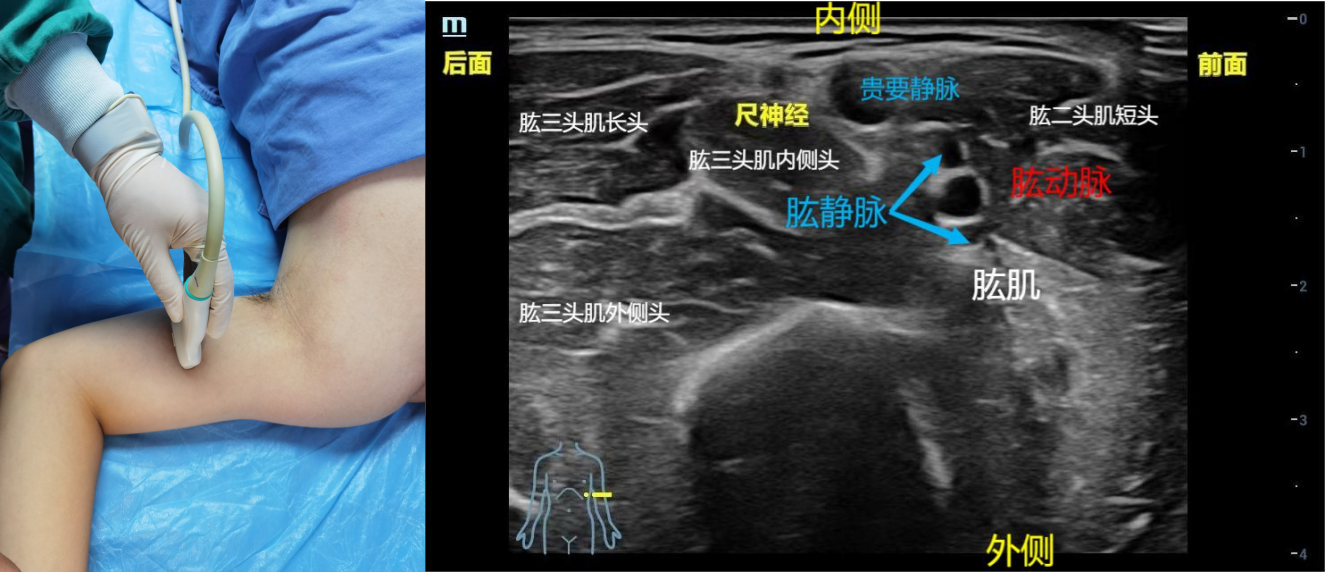

2、肱骨中段入路:体位:平卧位,手臂外展90°。步骤:探头先在肘关节处找到尺神经,然后向上追踪,在肱骨中上1/3处,尺神经在肱骨中段非常表浅(一般在皮下就可见),也和贵要静脉靠得很近。准确的位置是肱二头肌的内侧,肱动脉的后侧,圆形高回声的图像,为肱骨中段的尺神经。平面内法,从探头前端进针,避免损伤肱动脉和肱动脉前侧的正中神经。药物用量:0.25%-0.5%罗哌卡因3-5ml。